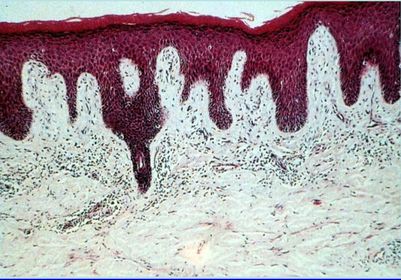

Diagnóstico PLACA PSORIÁSICA